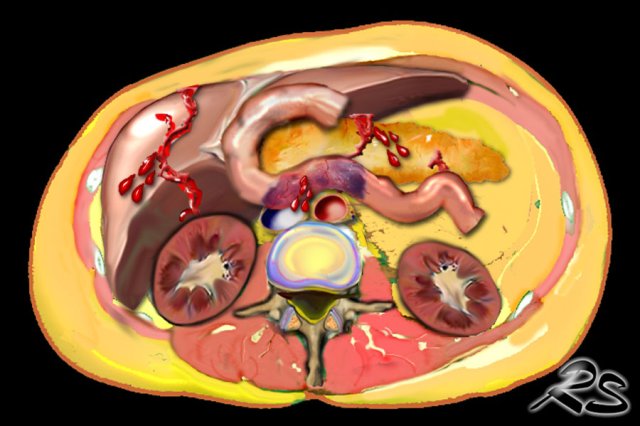

Abdominal injuries

In

general visceral injuries in children are rare, however when diagnosed common

abdominal injuries in abused children are:

- liver laceration

- duodenal hematoma

- pancreatic laceration

Image

The CT shows pancreatic laceration in child abuse.

These abdominal injuries are non-specific and could also be attributed to accidental injury.

However in most of these cases of child abuse, there is a history that does not correlate well with the injuries, that are found.

So you have to look for other more specific skeletal injuries in these children.

Liver laceration in child abuse